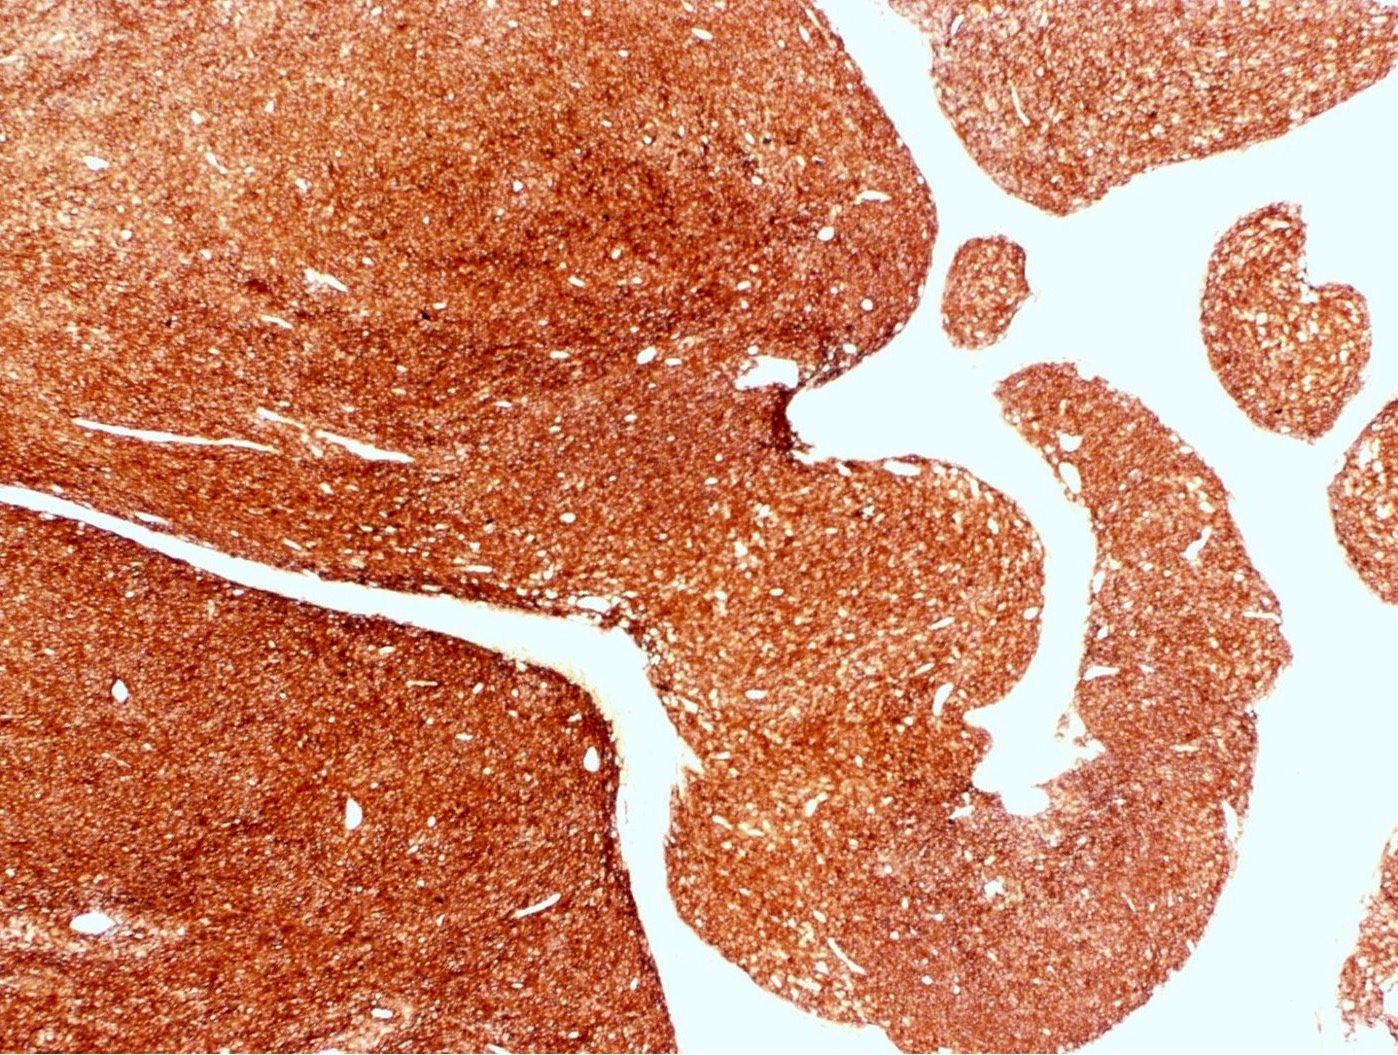

Microscopic (histologic) description

- Irregular cellular islands, forming permeative tongue-like pattern of myometrial invasion with frequent vascular invasion

- Monotonous oval to spindle cells with minimal cytologic atypia, vesicular chromatin and scant cytoplasm

- Mitotic count is usually low (< 5/10 high power fields), necrosis is usually absent

- Tumor cells may whorl around delicate arteriolar type vessels, reminiscent of proliferative phase endometrial stroma

Microscopic (histologic) images

Contributed by Elizabeth Kertowidjojo, M.D., Ph.D., M.P.H. and Ayse Ayhan, M.D., Ph.D.

Positive stains